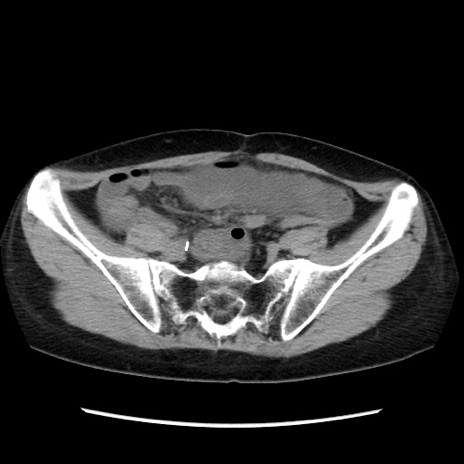

冠状断像

矢状断像